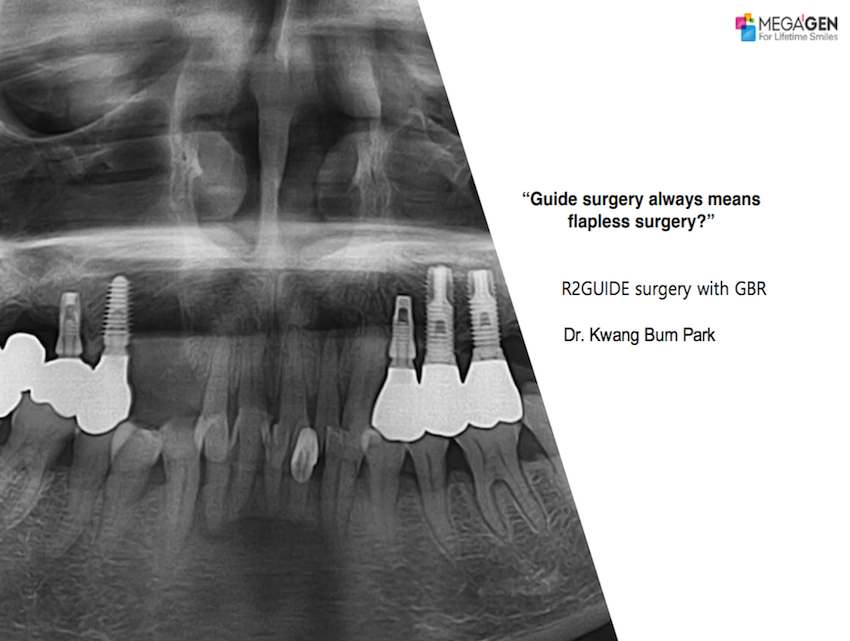

#26,AnyRidge,Bone regeneration,Digital Guided Surgery,Dr. Antonio Cabral de Campos Felino,Dr. Isabel Maria Lopes Guerra,Dr. Mario Ramalho de Vasconcelos,Dr. Raquel Zita Gomes,Dr. Rute Alexandra Borges de Almeida,Immediate Placement,Maxillary Posterior,MEGA ISQ,Publication,R2GATE,R2GATE Guide,Single replacement,Xpeed